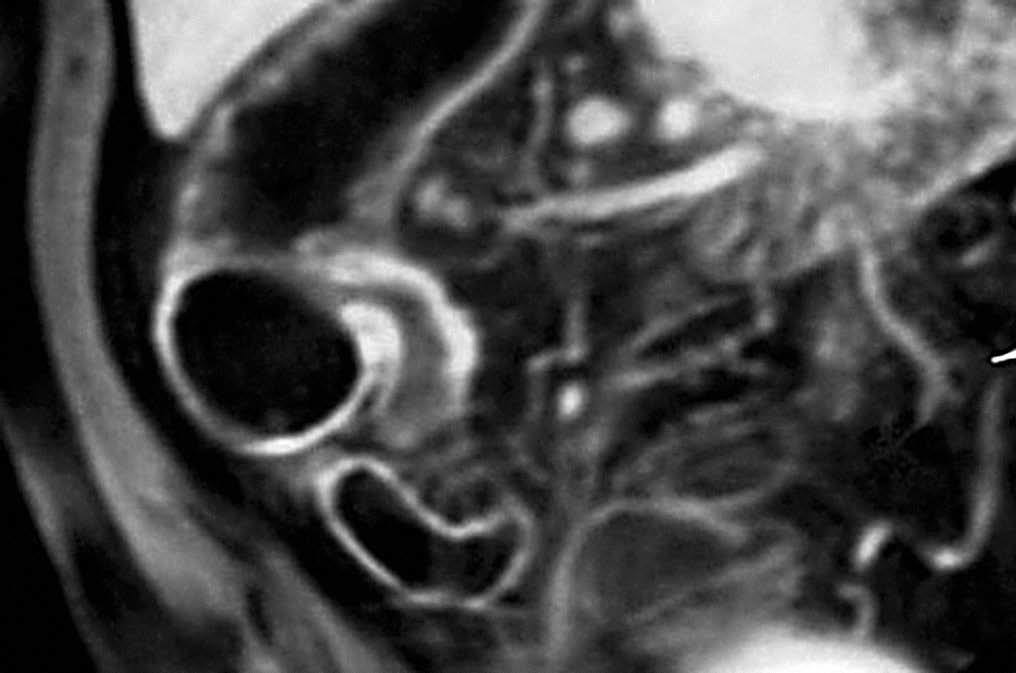

Los hallazgos en la TC y la RM sugestivos de EC en fase activa son la hiperemia, característica de un proceso inflamatorio y la estratificación de la pared intestinal (fig. 8). El concepto de hiperemia que depende de la prominencia, tortuosidad y dila-tación de los vasa recta, se traduce por el signo del "peine" (fig. 9), descrito por Meyers y McGuire16 en estudios tomodensitométricos de pacientes en fase activa de la EC. Si bien no es un signo patognomónico de la EC, la hiperemia a nivel de las asas intestinales es marcador de actividad17. La estratificación de la pared intestinal justifica un aspecto en "diana" (fig. 3B) con una zona de alto valor de atenuación interna que corresponde a la mucosa, otra zona también de alto valor de atenuación periférica que corresponde a la muscular-serosa y una zona intermedia entre ambas, de menor valor de atenuación que corresponde a la submucosa edematosa en relación con la ectasia linfática12.

Fig. 8.--Ileocolitis granulomatosa. (A) La resonancia magnética (RM) en secuencia potenciada en T1, tras la administración de gadolinio endovenoso, en corte de orientación axial, muestra engrosamiento mural del íleon terminal y del polo cecal que se realza con contraste. (B) Correlación en el plano coronal.